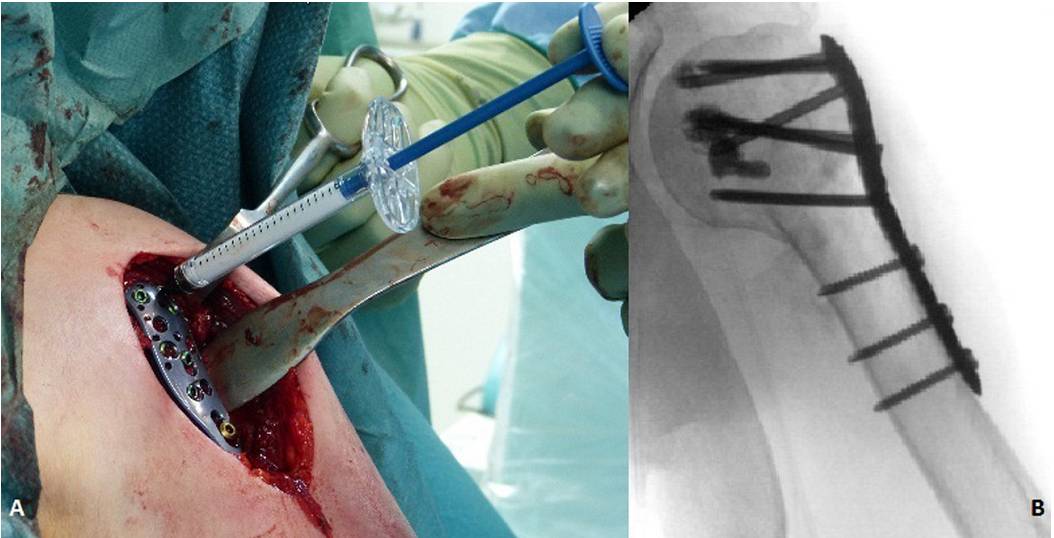

图1.

肱骨近端骨折锁定钢板固定时,内侧支撑螺钉(黑色箭头)维持肱骨内侧柱稳定性。